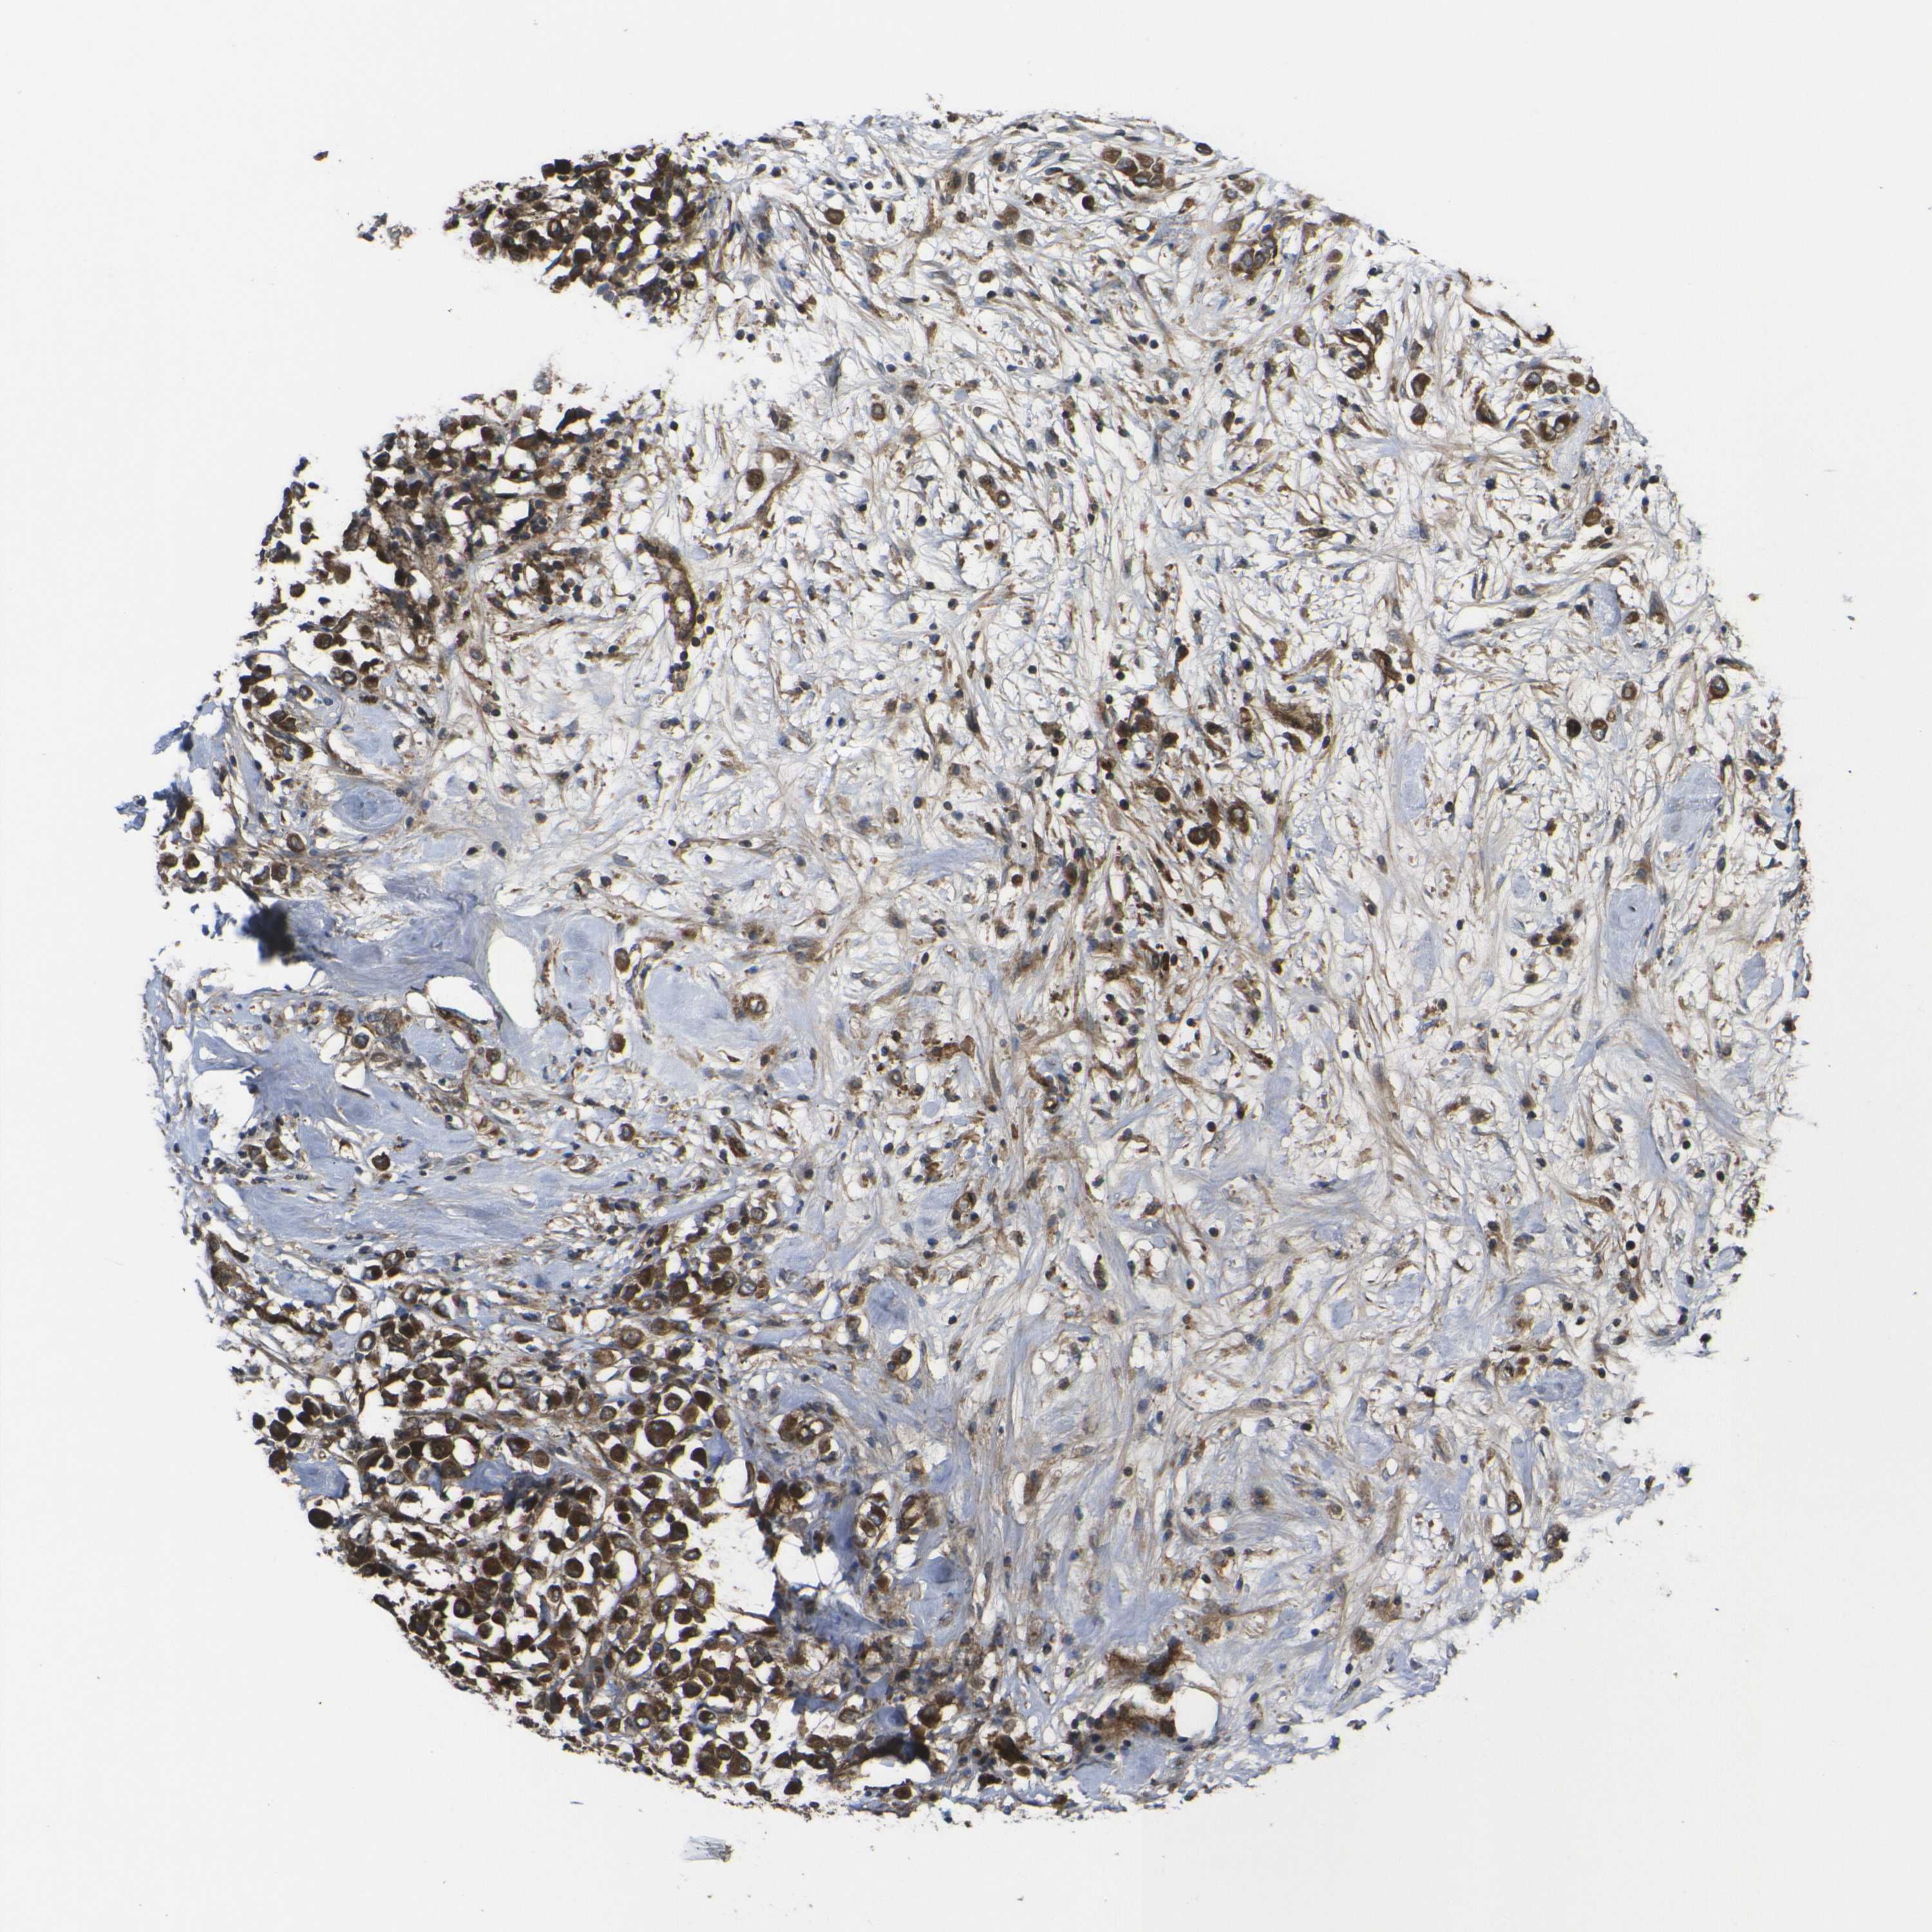

CANCER BREAST CANCER Show tissue menu

BRCA TCGA BRCA VALIDATION PROTEIN EXPRESSION